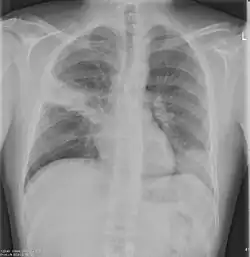

Chest X-rays and X-ray computed tomography (CT) can reveal areas of opacity (seen as white), indicating consolidation.[14] CAP does not always appear on x-rays, sometimes because the disease is in its initial stages or involves a part of the lung not clearly visible on x-ray. In some cases, chest CT can reveal pneumonia not seen on x-rays. However, congestive heart failure or other types of lung damage can mimic CAP on x-ray.[16]

Chest X-rays of a CAP patient before (left) and after treatment

CAP is treated with an antibiotic that kills the infecting microorganism; treatment also aims at managing complications. If the causative microorganism is unidentified, which is often the case, the laboratory identifies the most effective antibiotic; this may take several days.